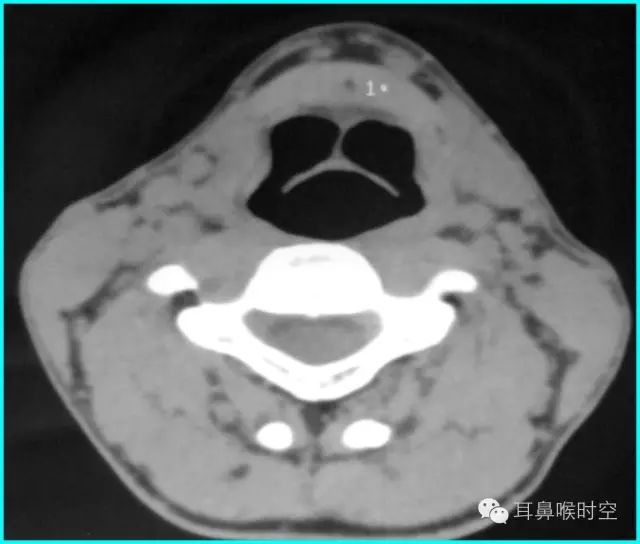

(3)喉咽腔层面:

标准CT 轴位像:

鼻咽气腔形态因层面不同而不同,其中,呈梯形(图3),长方形(图4)。

咽隐窝及咽鼓管咽口清晰或隐约可见,双侧对称,鼻后孔大部分畅通,咽旁间隙清晰,邻近骨质无破坏。